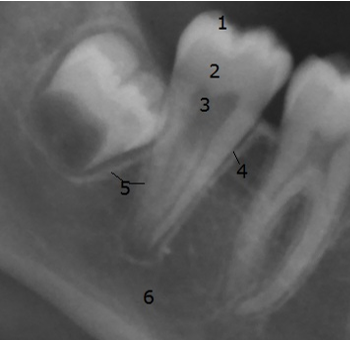

The radiological criteria of lower third molar investigation were: presence and extension of periodontal space (Figure 4 [Fig. 4]), alveolar (periodontal) bone loss (Figure 5 [Fig. 5]), emergence of tooth (Figure 3 [Fig. 3], Figure 5 [Fig. 5] and Figure 6 [Fig. 6]), and stage of tooth mineralization (Figure 7 [Fig. 7]). Teeth were identified according to the dental scheme proposed by Féderation Dentaire International (FDI) including a consecutive numbering of both the teeth and the related quadrant of the jaws. The visibility of the periodontal space was staged according to proposals of Olze et al. [75] (Table 2 [Tab. 2]). In order to allow the evaluation of this item independent from the development stage of the tooth, this stage grouping was modified with respect to a certain radiological finding: the periodontal space is a fine radiotranslucent structure delineating the dental root from the surrounding bone. On radiographs, the jaw’s border to the periodontal space is frequently marked by a finely drawn radiopaque line entitled ‘lamina dura’ [24]. This radiological term can be applied to teeth with developing roots and also in the cases of completely mineralized teeth (Figure 7 [Fig. 7]). Alveolar bone loss was estimated according to Olze et al. [77] (Table 3 [Tab. 3]).

Figure 5: Cropped image of orthopantomogram showing lower molars of the right side. The third molar’s crown is radiologically of full radiopacity, the enamel to dentine border can be seen and roots are not developed: a continuous radiopaque line surrounds the developing tooth (1 = enamel, 2 = dentine, 3 = pulp cavity, 4 = periodontal space, 5 = lamina dura, 6 = cortical bone (lower border of mandible).